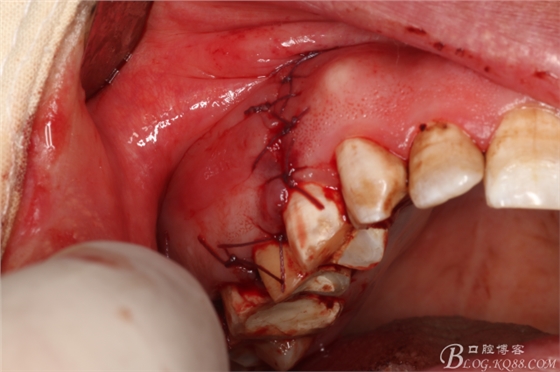

圖18.縫合